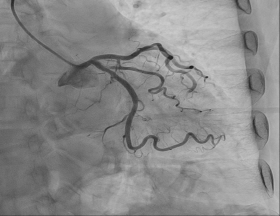

관상동맥 조영술 |